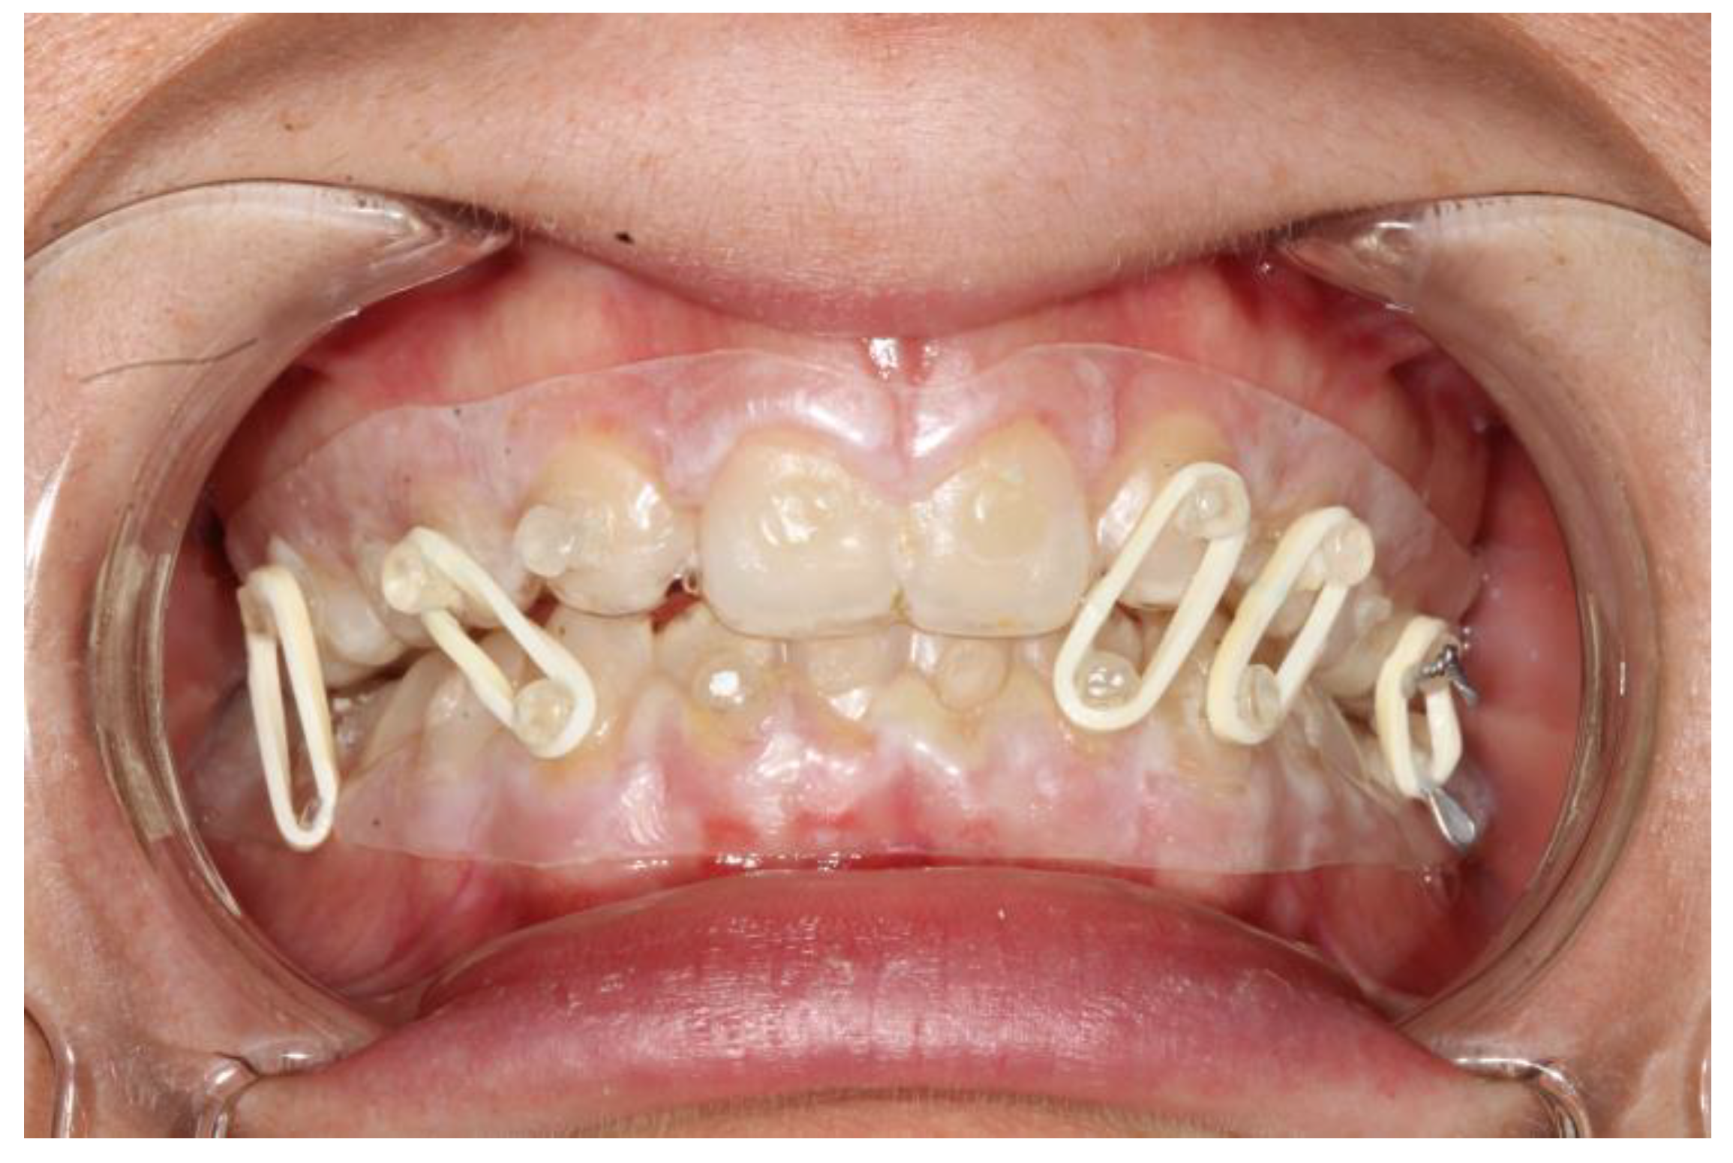

The splints were bonded to the teeth with a restorative flowable composite (Filtek Supreme Flowable, 3M, St. Paul, MN, USA), which was applied through the holes designed on the splint (Figure 1 and Figure 2).

Figure 1. Intraoral view of patient 2. It is possible to see the coronal fracture of element 4.2; the fitting of the splints is adequate and so is the fixation.

The second patient was a male, aged 20, with a right condylar diacapitular fracture (Figure 4). The patient also presented a coronal fracture of the element 43 due to the trauma. The other teeth were sound, but the 37 was unerupted. He presented a slight class III malocclusion and a posterior open bite on the left. In this case, there was the need to not exert force on the fractured tooth, and to balance the traction points of the rubber bands despite the absence of the 37, avoiding extrusive forces on the 27.

The fixation strength of the intermaxillary fixation was considered adequate in both cases (Figure 5 and Figure 6).